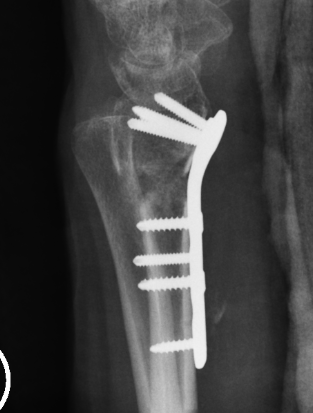

Dorsal opening wedge osteotomy

Advantage

Lengthens the distal radius

May be easier to correct in coronal and sagittal plane

Disadvantage

Dorsal approach / dorsal plate - extensor tendon issues

Technique

3 / 4 dorsal approach

- expose distal radius

- can use half pins to control distal fragment

- protect structures with homan retractors

- osteotomy with microsagittal saw

- correct radial articular surface in sagittal & coronal planes

- trapezoidal bi-cortical iliac crest autograft / synthetic graft

- dorsal locking plate